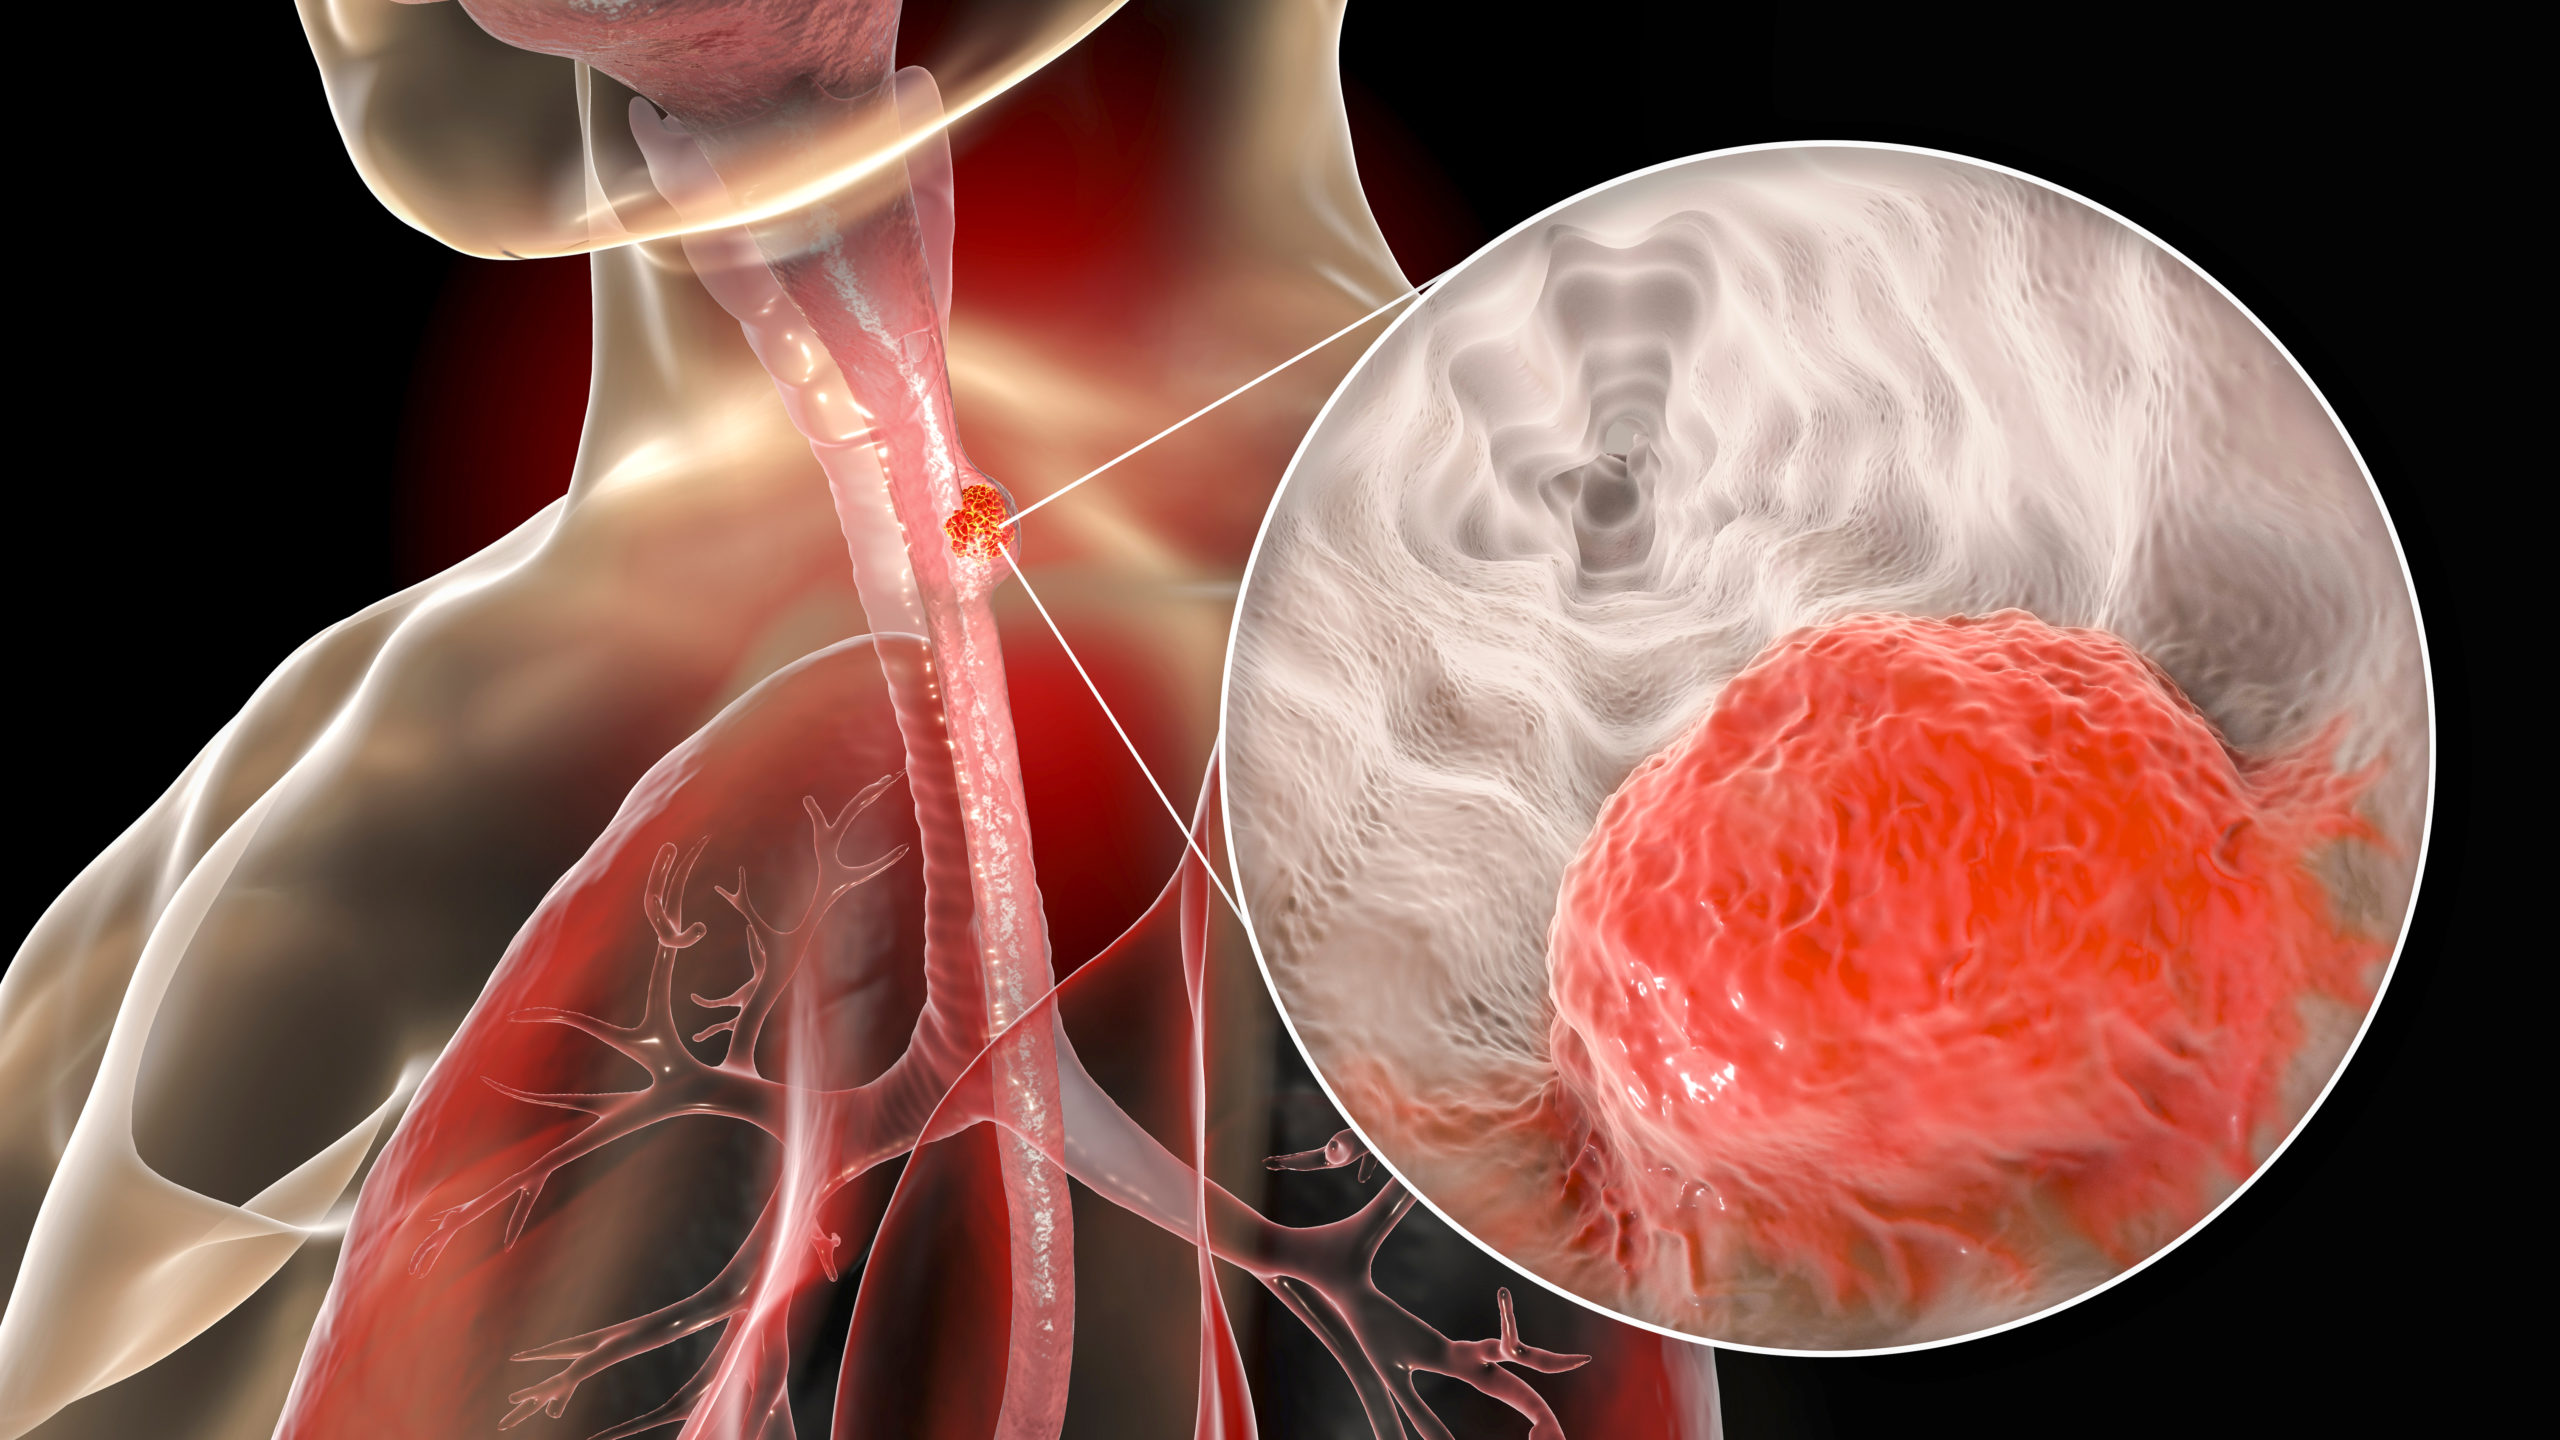

In a randomized controlled trial, published in the Journal of Cancer Research and Therapeutics, researchers compared ...Patrick DalyGastric Cancer | May 16, 2022

Researchers performed a randomized clinical trial to examine the efficacy of bevacizumab and gemcitabine plus cisplatin ...Patrick DalyColorectal Cancer | May 4, 2022